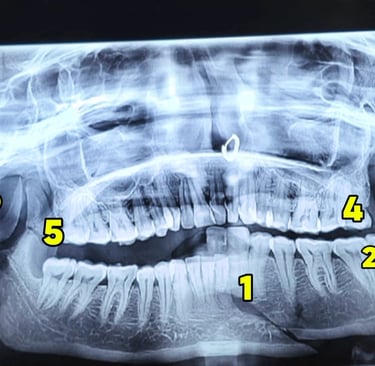

Radiographic Diagnosis: Orthopantomogram (OPG) was performed, which revealed multiple mandibular fractures involving:

Right angle region

Parasymphysis region

Bilateral condylar involvement

Coronoid fracture

Total of 6 fracture segments